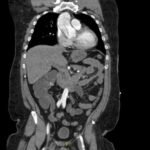

Acute aortic dissection is a life-threatening event caused by separation of the aortic layers that requires prompt management and surgical consultation. We present the case of a 53-year-old male who developed acute, severe chest pain radiating to his back at a community hospital and was transferred to a tertiary center for definitive surgical management. The patient’s aortic dissection was diagnosed via computed tomography angiography. He was started on rate-control and blood pressure medications, and was admitted emergently to the operating room. Emergency physicians should obtain immediate surgical consultation, promptly start medications for rate and blood pressure control, and administer analgesia in order to stabilize their patient and decrease the shear forces that would further propagate an aortic dissection.